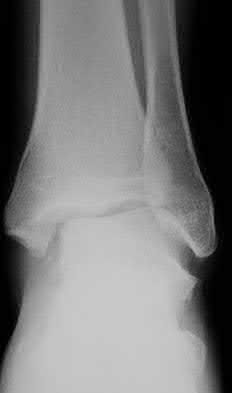

4. # After undergoing the treatment seen in Figure A, when should a patient be expected to safely operate the brakes of an automobile?

Corrent answer: 4

Figure A shows a patient after an open reduction and internal fixation of a bimalleolar ankle fracture.

Egol et al showed that by nine weeks, the total braking time of patients who had undergone fixation of a displaced right ankle fracture returns to the normal, baseline value.

Egol et al, also found that appropriate braking time returns at a point 6 weeks after initiation of weightbearing after treatment of lower extremity long bone and periarticular fractures, as examined with a driving simulator. No differences were seen in return of braking time between periarticular fractures and long bone injuries.